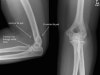

X-ray : 요골두 골절(Radial head fracture)

보통 AP, lateral, both oblique 즉 4장의 사진을 모두 찍어야 미세한 골절을 찾아내기 수월합니다.

필요시 요골두-소두 촬영을 실시합니다.